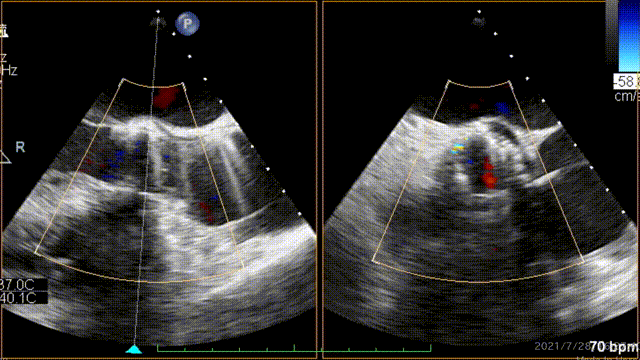

术前超声心动图示:

1.主动脉瓣钙化、粘连;

2.主瓣狭窄(重度)伴主瓣关闭不全(轻中度);

3.二、三尖瓣轻度返流;

术前:LVEF:64%;

主动脉瓣:峰值流速5.1m/s,峰值压差104mmHg;平均跨瓣压差59mmHg。

术中经食道心超评估:

人工主动脉瓣:植入深度 7mm,峰值流速1.2m/s,峰值压差6mmHg,平均跨瓣压差3mmHg,原左-右冠窦结合部微量瓣周漏。